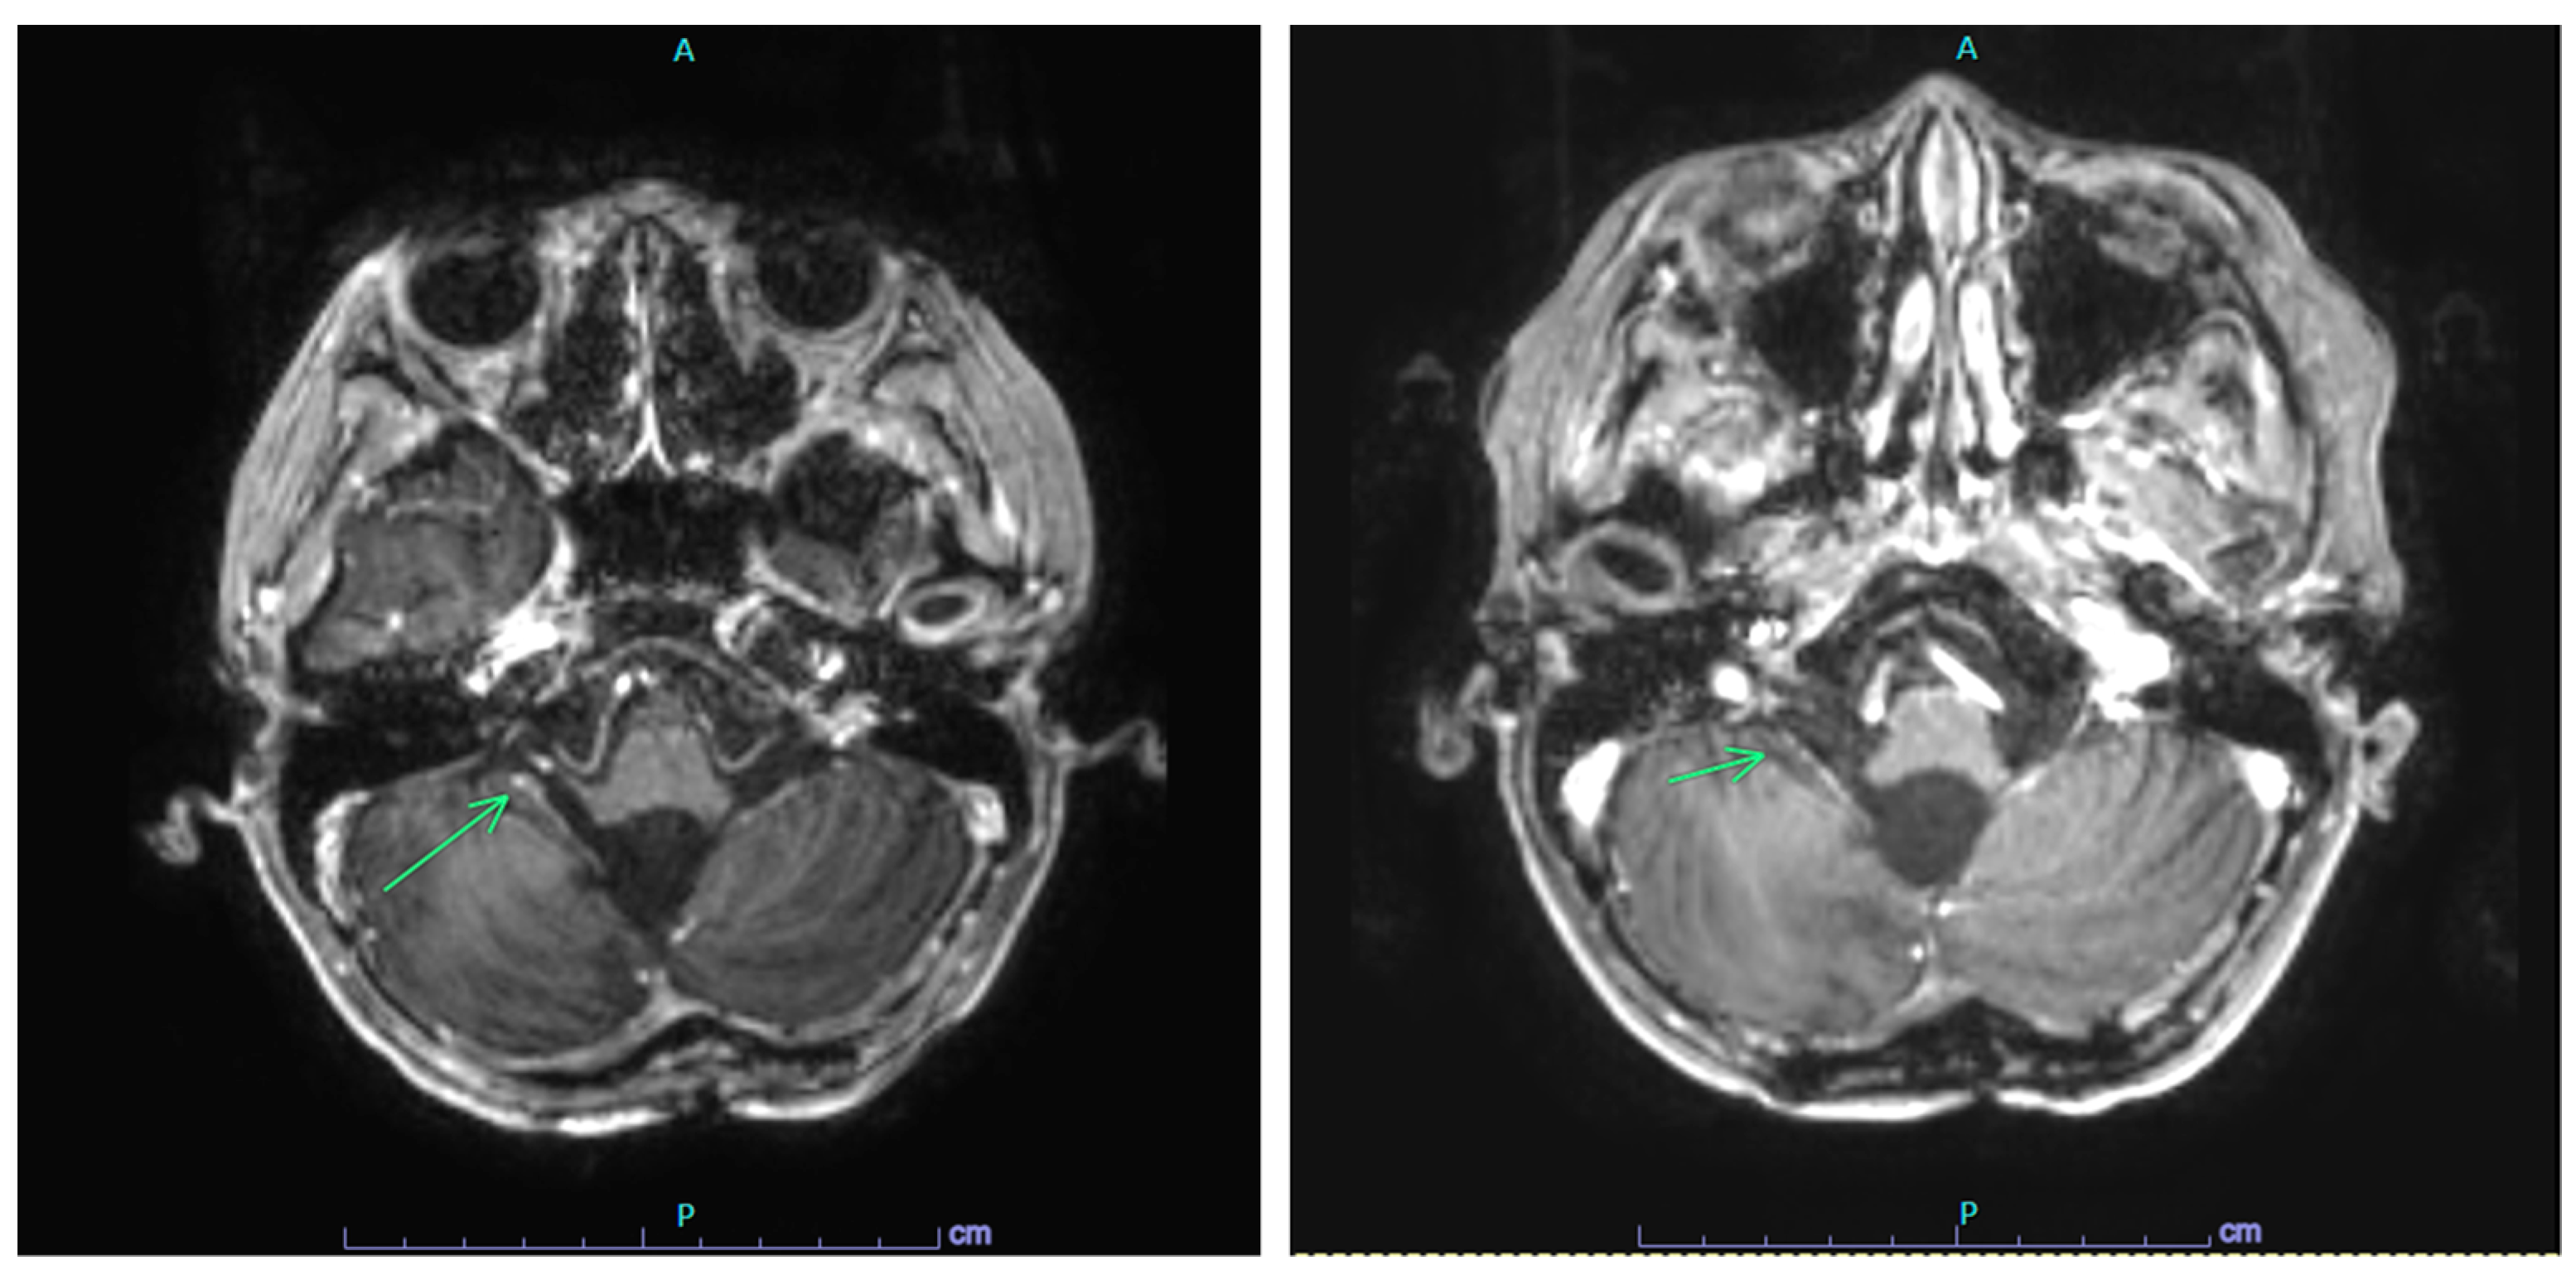

2.1. Case 1